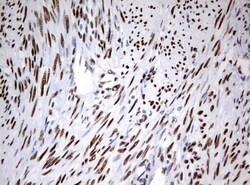

- Submitted by

- Invitrogen Antibodies (provider)

- Main image

- Experimental details

- Immunohistochemical staining of paraffin-embedded Adenocarcinoma of Human breast tissue using anti-ZSCAN18 mouse monoclonal antibody. (UM500081; heat-induced epitope retrieval by 10mM citric buffer, pH6.0, 120°C for 3min)